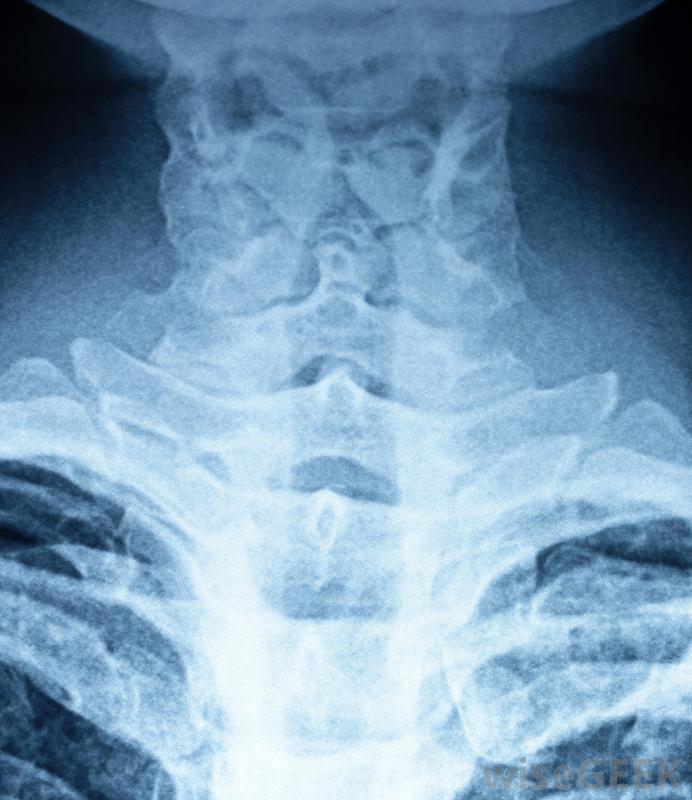

喉部CT(計算機斷層掃描)是一種診斷成像工具,用于評估喉部并檢測各種可能顯示疾病和疾病的標記物,從炎癥到惡性腫瘤。與其他類型的CT掃描類似,喉部CT掃描涉及放射治療,這可能會增加患者患癌癥的風險長期的,如果病人接受多次掃描。與任何非侵入性診斷測試一樣,在測試之前,代表患者幾乎不需要做任何準備。一般來說,只要結果在正常范圍內,就很少進行額外的檢查喉部CT掃描可生成頸部、頭部和肩部的圖像。有時也稱為喉部掃描,喉部CT使用X射線來產生多個喉部內部的圖像。這些圖像從多個角度拍攝,作為一個整體進行編譯和檢查,以檢查疾病和疾病的跡象。在測試過程中使用對比染料以獲得盡可能完整的圖像并不少見喉嚨的異常腫脹可能需要進行CT掃描。在進行喉部CT掃描時,病人被安置在一個可移動的檢查床上,就像CT掃描儀一樣,在測試之前,檢查床會滑入隧道,在那里它保持原位,直到測試完成測試時,掃描器的X光設備會環繞患者的頭部和頸部區域拍攝咽喉圖像。每個角度都會拍攝一張快照圖像。一旦所有目標區域都被X射線捕獲,測試就完成了,圖像被用來制作喉嚨內部的三維圖像可進行喉部CT掃描,以評估和診斷咽喉狀況。進行喉部CT檢查是否存在異常在喉嚨內。個人可以接受喉部掃描以確定感染的存在或程度。如果喉部有明顯的炎癥,可以進行CT掃描以確定其原因。其他可能需要進行喉部掃描的情況包括動脈問題和異常腫脹或腫塊。這種情況并不少見當對頸部和喉部進行某些類型的活檢時,喉部CT掃描可作為指導。喉部CT掃描是評估咽部的診斷工具如果使用對比染料,有多種給藥方法。通常,對比劑在測試前口服。口服染料通常呈乳白色,口感呈白堊狀,給藥后幾個小時內就作為廢物排出體外。其他的染料輸送方法包括靜脈注射和直腸注射有些人可能會被要求在染料相關檢測之前暫時停止使用某些藥物,以盡量減少喉部CT掃描中相互作用和并發癥的風險。喉部CT掃描會產生喉嚨內部的多張圖像。